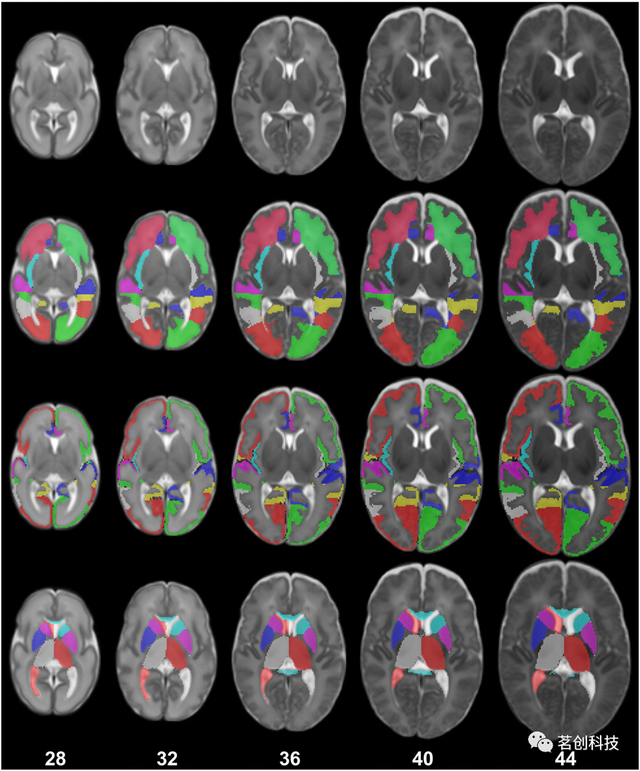

UNC婴儿0-1-2图谱

这是一套针对新生儿、一岁和两岁婴幼儿的纵向时空图谱,共95名。这些新生儿在出生后五周内进行了首次扫描,并在一岁和两岁时进行了纵向扫描。这种纵向设计是避免选择偏差的一个重要特征,这在横截面设计中是不可避免的。该图谱由组平均T1和T2加权图像组成,其中包括灰质、白质和脑脊液的组织概率图,这些图像是使用应用于每张图像的自动图像分割方法创建的。该图集还包含从自动解剖标记(AAL)传播的分割图谱。

来源:Infant brain atlases from neonates to 1- and 2-year-olds.

UNC纵向0-3-6-9-12个月大的婴儿图谱

这是一组典型的0、3、6、9和12个月大的婴儿时空图谱,由35名健康婴儿组成,这些婴儿每三个月进行一次纵向扫描,直到一岁。该图谱由组平均T1和T2加权图像组成,其中包括灰质、白质和脑脊液的组织概率图。其主要意义在于同时引入了时间和空间约束,以生成具有丰富结构细节和纵向一致性的图集。纳入了3个月、6个月和9个月的图谱有助于分析婴儿MRI,因为在生命的第一年,大多数大脑区域的灰质和白质之间的T1和T2加权对比度仍然很差。

来源:Consistent spatial-temporal longitudinal atlas construction for developing infant brains.